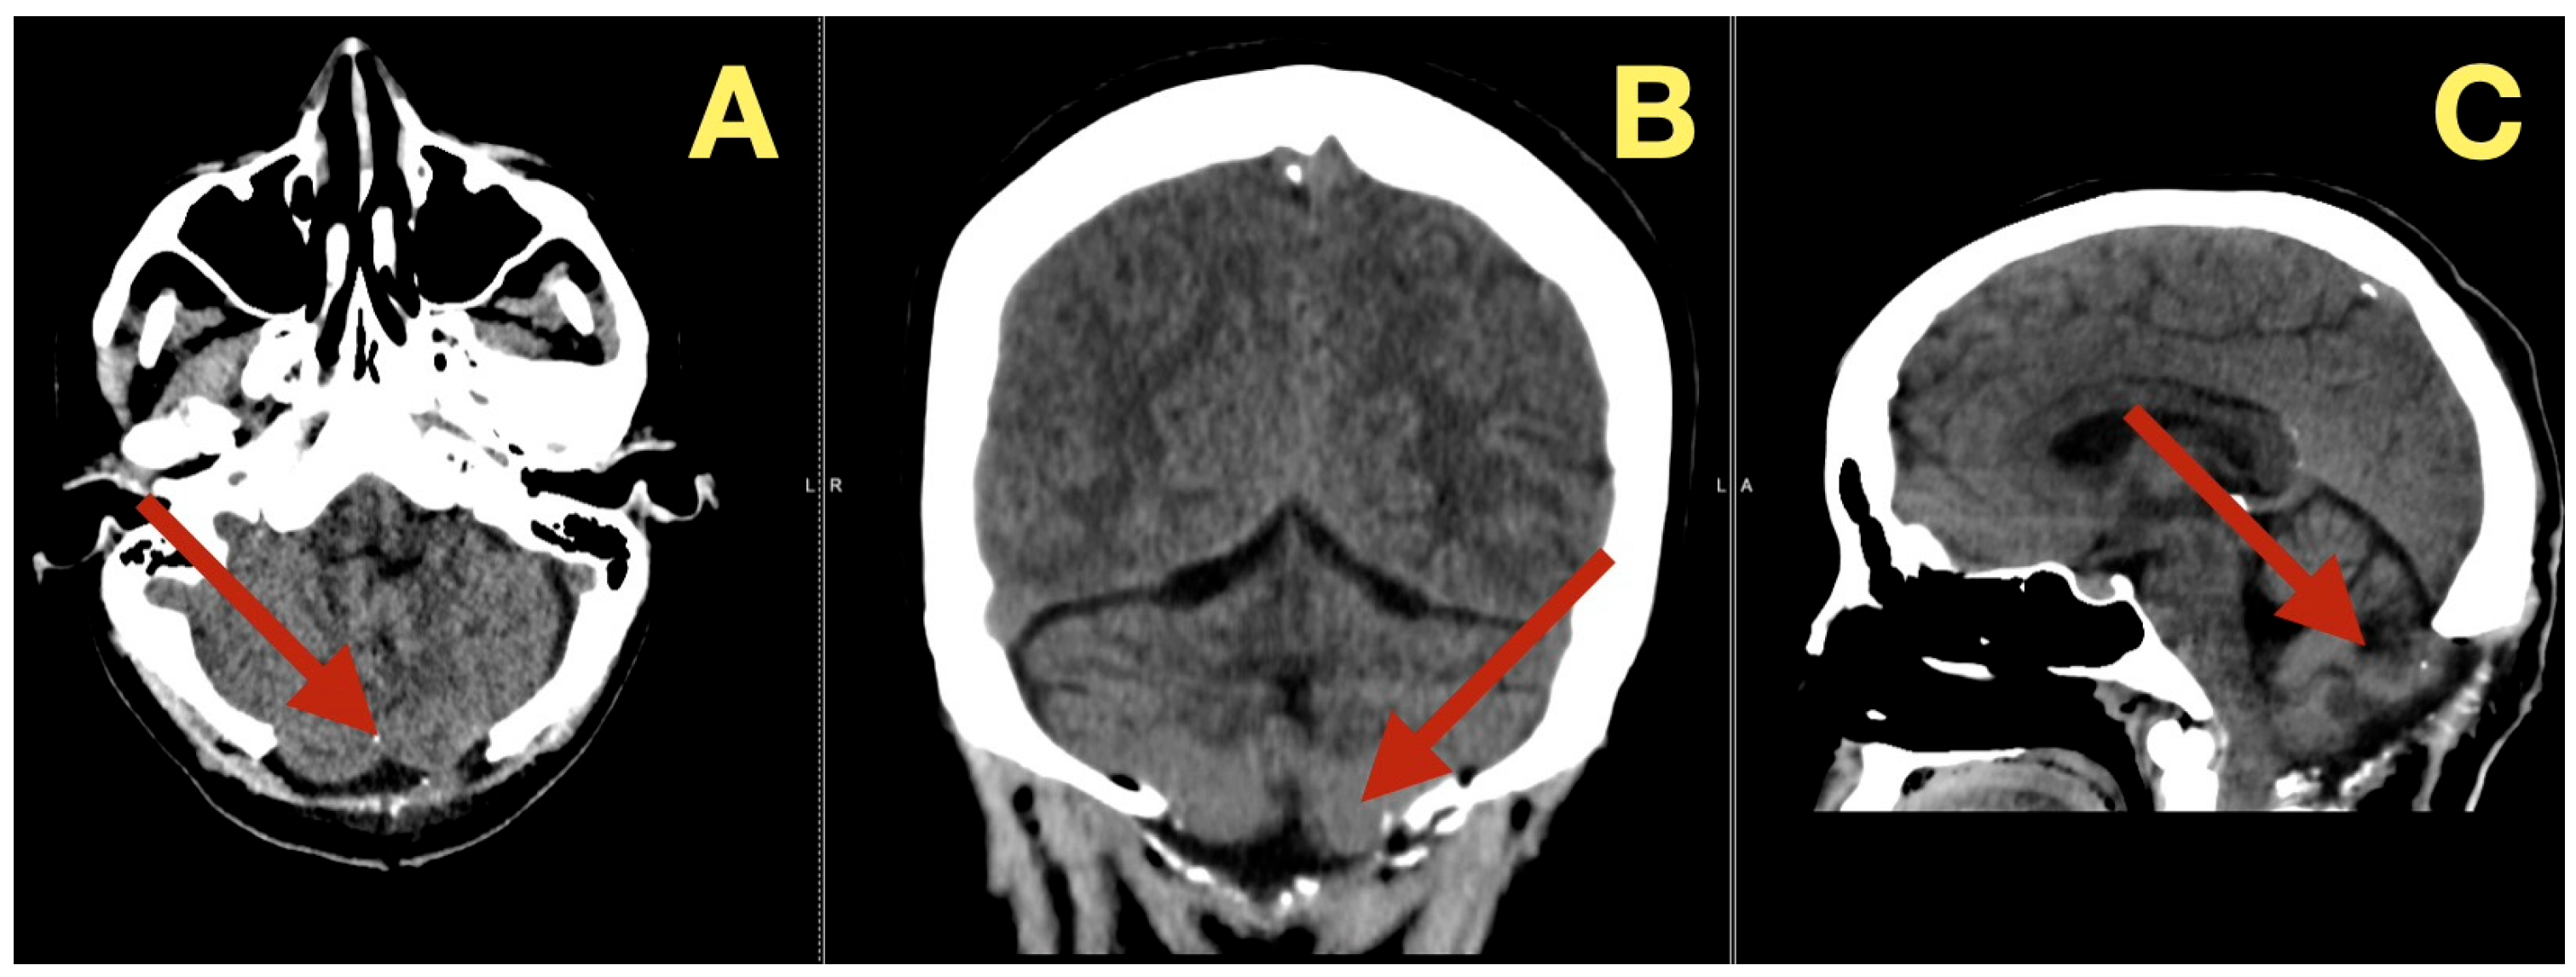

In addition to its rarity, the case also stood out due to the fact that all of the patient’s preoperative angiograms revealed a normal architecture of cerebral vasculature and no indication of aneurisms, arteriovenous malformations, or impaired venous outflow (Figure 2A,B). Further, the Circle of Willis was fully developed and symmetrically distributed, and the dural venous sinuses were unobstructed. As such, these studies ruled out vascular-related causes of intracranial hypertension and were consistent with a slowly expanding, avascular lesion.

CT scans completed on the first post-operative day (Figure 3) were utilized to exclude hemorrhage and assess early ventricular diameter; they indicated posterior fossa re-expansion, full reopening of the fourth ventricle, normal brainstem convexity, and no early hydrocephalus. A second CT scan completed 7 days post-operatively (Figure 4) verified stable ventricular and outlet patency and excluded late onset hydrocephalus. The one month follow-up CT scan (Figure 5) provided a baseline for long-term comparisons. Later surveillance relied upon MRI including DWI to exclude diffusion-positive residual or recurrence.

Figure 3. Immediate postoperative CT scan. (A): Axial CT showing full decompression of the fourth ventricle and restoration of normal CSF circulation (arrow). (B): Coronal CT demonstrating complete midline re-expansion with absence of residual mass (arrow). (C): Sagittal CT confirming brainstem relaxation and normalization of posterior-fossa anatomy (arrow).

Diagnostics 16 00129 g003